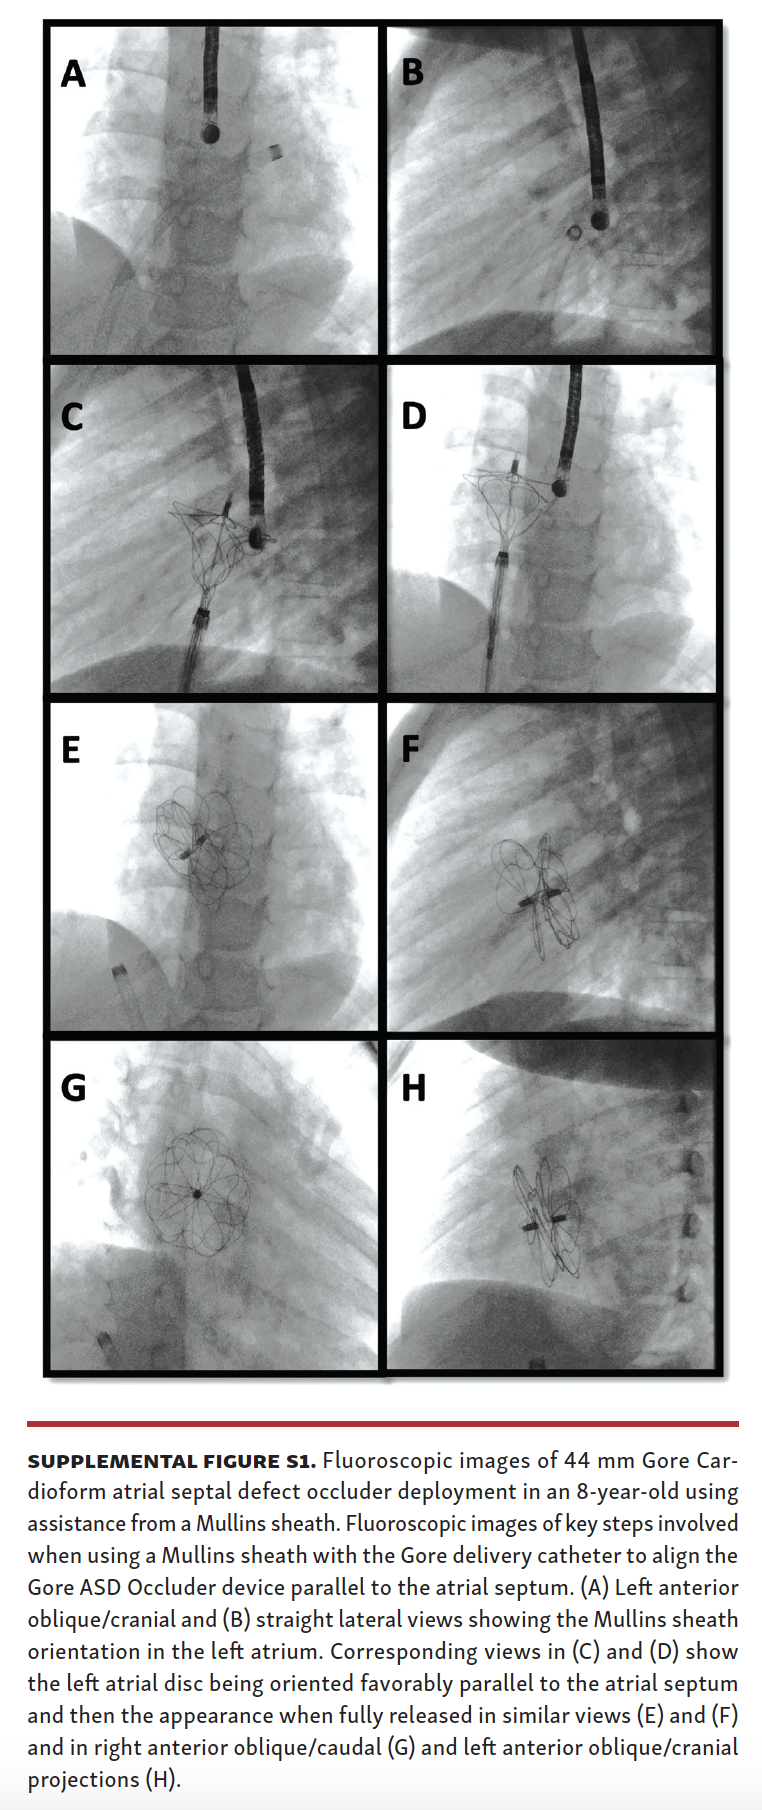

MullinsSheath Facilitated Delivery of Gore Cardioform ASD Occluder Asd Closure Device Ct atrial septal defect (asd) devices are typically below a line drawn from the carina to the cardiac apex in a lateral radiograph. device closure is a safe and effective procedure in experienced hands, with major complications such as cardiac perforation or device. figure 10 ct scan before percutaneous device closure. (a) axial oblique ct image shows as. Asd Closure Device Ct.

From www.hmpgloballearningnetwork.com